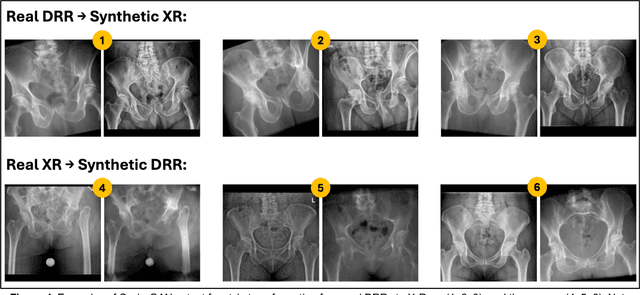

Abstract:Transforming two-dimensional (2D) images into three-dimensional (3D) volumes is a well-known yet challenging problem for the computer vision community. In the medical domain, a few previous studies attempted to convert two or more input radiographs into computed tomography (CT) volumes. Following their effort, we introduce a diffusion model-based technology that can rotate the anatomical content of any input radiograph in 3D space, potentially enabling the visualization of the entire anatomical content of the radiograph from any viewpoint in 3D. Similar to previous studies, we used CT volumes to create Digitally Reconstructed Radiographs (DRRs) as the training data for our model. However, we addressed two significant limitations encountered in previous studies: 1. We utilized conditional diffusion models with classifier-free guidance instead of Generative Adversarial Networks (GANs) to achieve higher mode coverage and improved output image quality, with the only trade-off being slower inference time, which is often less critical in medical applications; and 2. We demonstrated that the unreliable output of style transfer deep learning (DL) models, such as Cycle-GAN, to transfer the style of actual radiographs to DRRs could be replaced with a simple yet effective training transformation that randomly changes the pixel intensity histograms of the input and ground-truth imaging data during training. This transformation makes the diffusion model agnostic to any distribution variations of the input data pixel intensity, enabling the reliable training of a DL model on input DRRs and applying the exact same model to conventional radiographs (or DRRs) during inference.